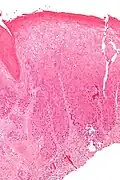

| Micrograph of (classic) vulvar intraepithelial neoplasia III. H&E stain. | |

Classic vulvar intraepithelial neoplasia: associated with developing into the warty and basaloid type carcinoma. This is associated with carcinogenic genotypes of HPV and/or HPV persistence factors such as cigarette smoking or immunocompromised states.

Micrograph of vulvar intraepithelial neoplasia III. H&E stain. -